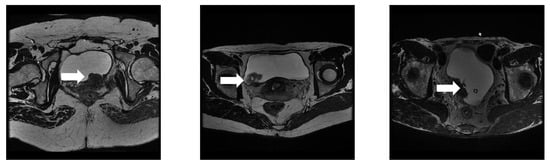

3.1. Dataset